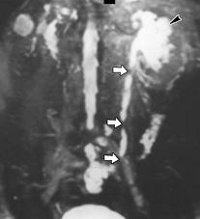

N13.5 Перегиб и стриктура мочеточника без гидронефроза